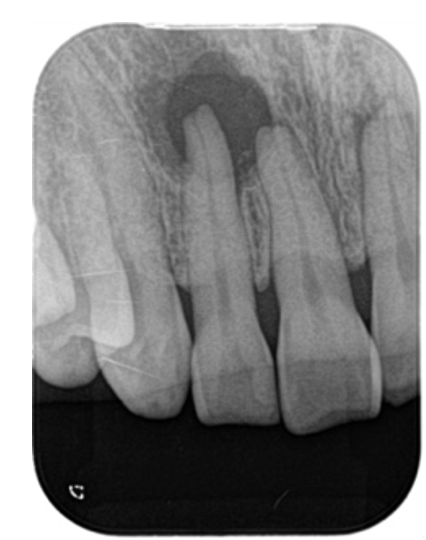

• 初診時、破折したファイルと、根を取り巻く黒い影がはっきりとわかります。

初診時、破折したファイルと、根を取り巻く黒い影がはっきりとわかります。

• 根管治療終了。根管のカーブしたところに食い込むように折れていますので、歯が薄くなるリスクをご説明し、外さない方向で治療を行いました。

根管治療終了。根管のカーブしたところに食い込むように折れていますので、歯が薄くなるリスクをご説明し、外さない方向で治療を行いました。

• 治療後8ヶ月経過 根の周りの黒い影は綺麗に消えて、治癒判定となりました。

治療後8ヶ月経過 根の周りの黒い影は綺麗に消えて、治癒判定となりました。